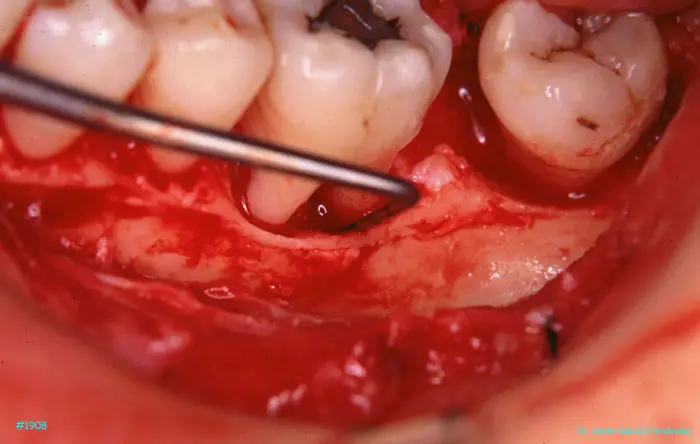

image 54